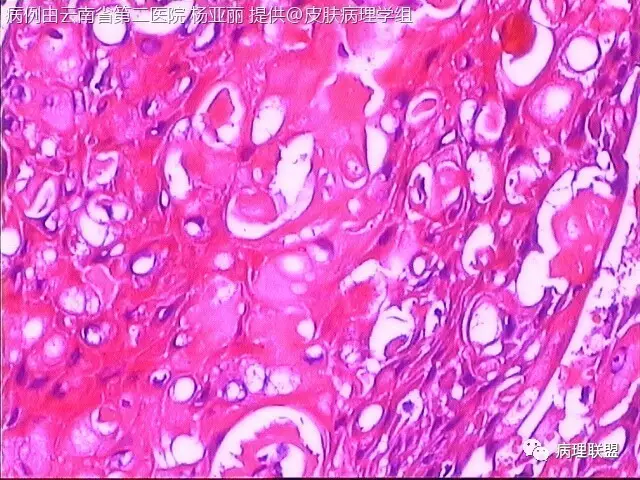

M/53 左手食指包块(皮肤鳞癌VS转移性鳞癌)

请各位老师帮忙看看,男性,53岁,左手食指包块 (病例由云南省第二医院 杨亚丽 提供,致谢!)

鳞癌没有问题。问题是否是转移癌:有否与表皮相连,病史演变如何?

@邓永键 谢谢邓主任,据说病人鼻子上有肿瘤才来切的手上的小包块,右手有,左手也有三四个,等我再问问鼻子上的是什么。看着细胞异型不明显,生长方式倒是确实不好。第6图有和表皮的关系,不相连,邓老师,鼻子上的肿瘤确实是鳞癌,这么说来手上的是转移的就很合理了。邓主任真是高,佩服!